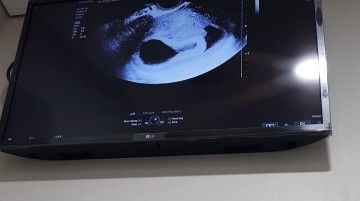

halo moms adakah yg usia kehamilannya 6 minggu blm keliatan janinnya juga? krn aku hr ini abis usg tv, kata dokter kantungnya sdh besar 2 cm lebih. tp dedenya blm muncul, baru hanya kantung dan cadangan makanannya aja. kata dokter juga biasanya harusnya udh ada janin dan kadang ada yg sudah ada djj nya. jd disuruh istirahat 1 minggu deh. cmn jd sedih dengernya🥲 huehehehe #bantusharing #seriusnanya #firstmom